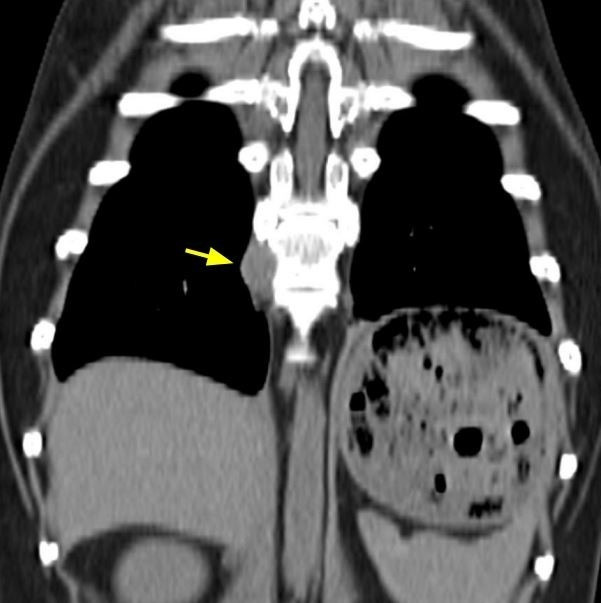

‘좌측 상완골의 골 융해, 증식이 동반된 광범위한 병변’

탁구의 상완골 CT 촬영 사진. 종양에 의해 뼈가 녹았다.

한 사진에 시선이 머물렀다. 왼쪽 어깨인 ‘상완골’의 CT 촬영 사진이었다. 믿을 수 없었다. 분명 어깨뼈의 형태를 하고 있는데 작은 구멍이 숭숭 나있었다. 쥐가 파먹은 치즈 혹은 염산에 부식된 철제 구조물처럼 보였다. 그제야 ‘좌측 상완골의 골 융해, 정상적인 형태 소실’이 무슨 의미인지 알게 됐다.

악성 종양은 커지면서 뼈를 녹인다고 했다. 탁구의 왼쪽 어깨뼈도 녹고 있었다. 그동안 탁구가 왜 왼쪽 다리를 접고 있었는지, 침을 놓을 때 미친 듯이 발버둥 쳤는지, 스테로이드 주사의 효과가 일시적이었는지 단번에 이해할 수 있었다.